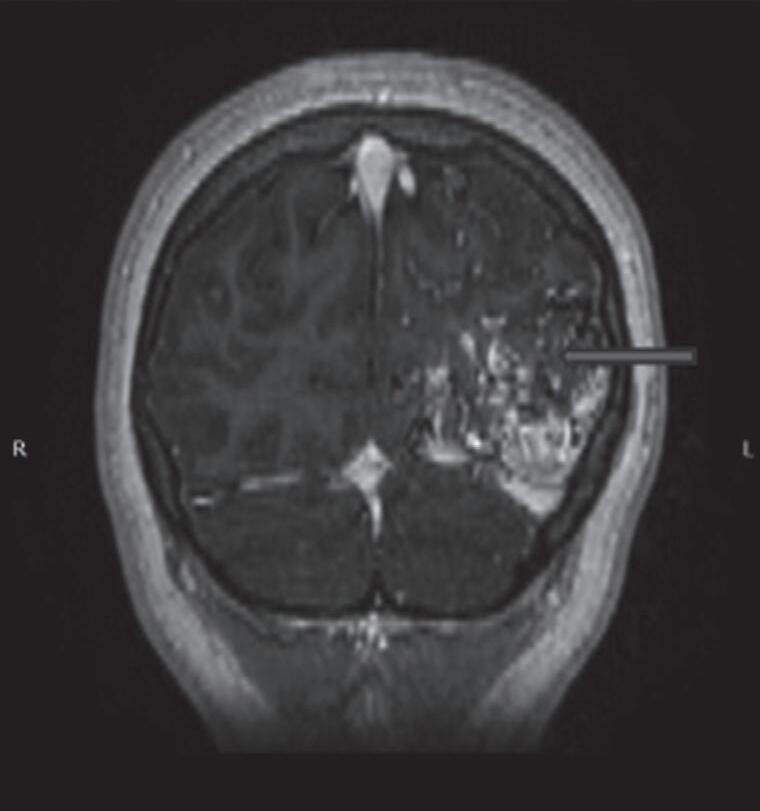

Fig. 1-17. RNM encéfalo T1 com contraste (a) axial e (b) T2 sagital demonstrando MAV grau 5 profunda temporoinsular esquerda com extensão nos núcleos da base. (c,d) Arteriografia cerebral,demonstrando a drenagem venosa profunda para veia cerebral interna (seta azul) com sinais de hipertensão.